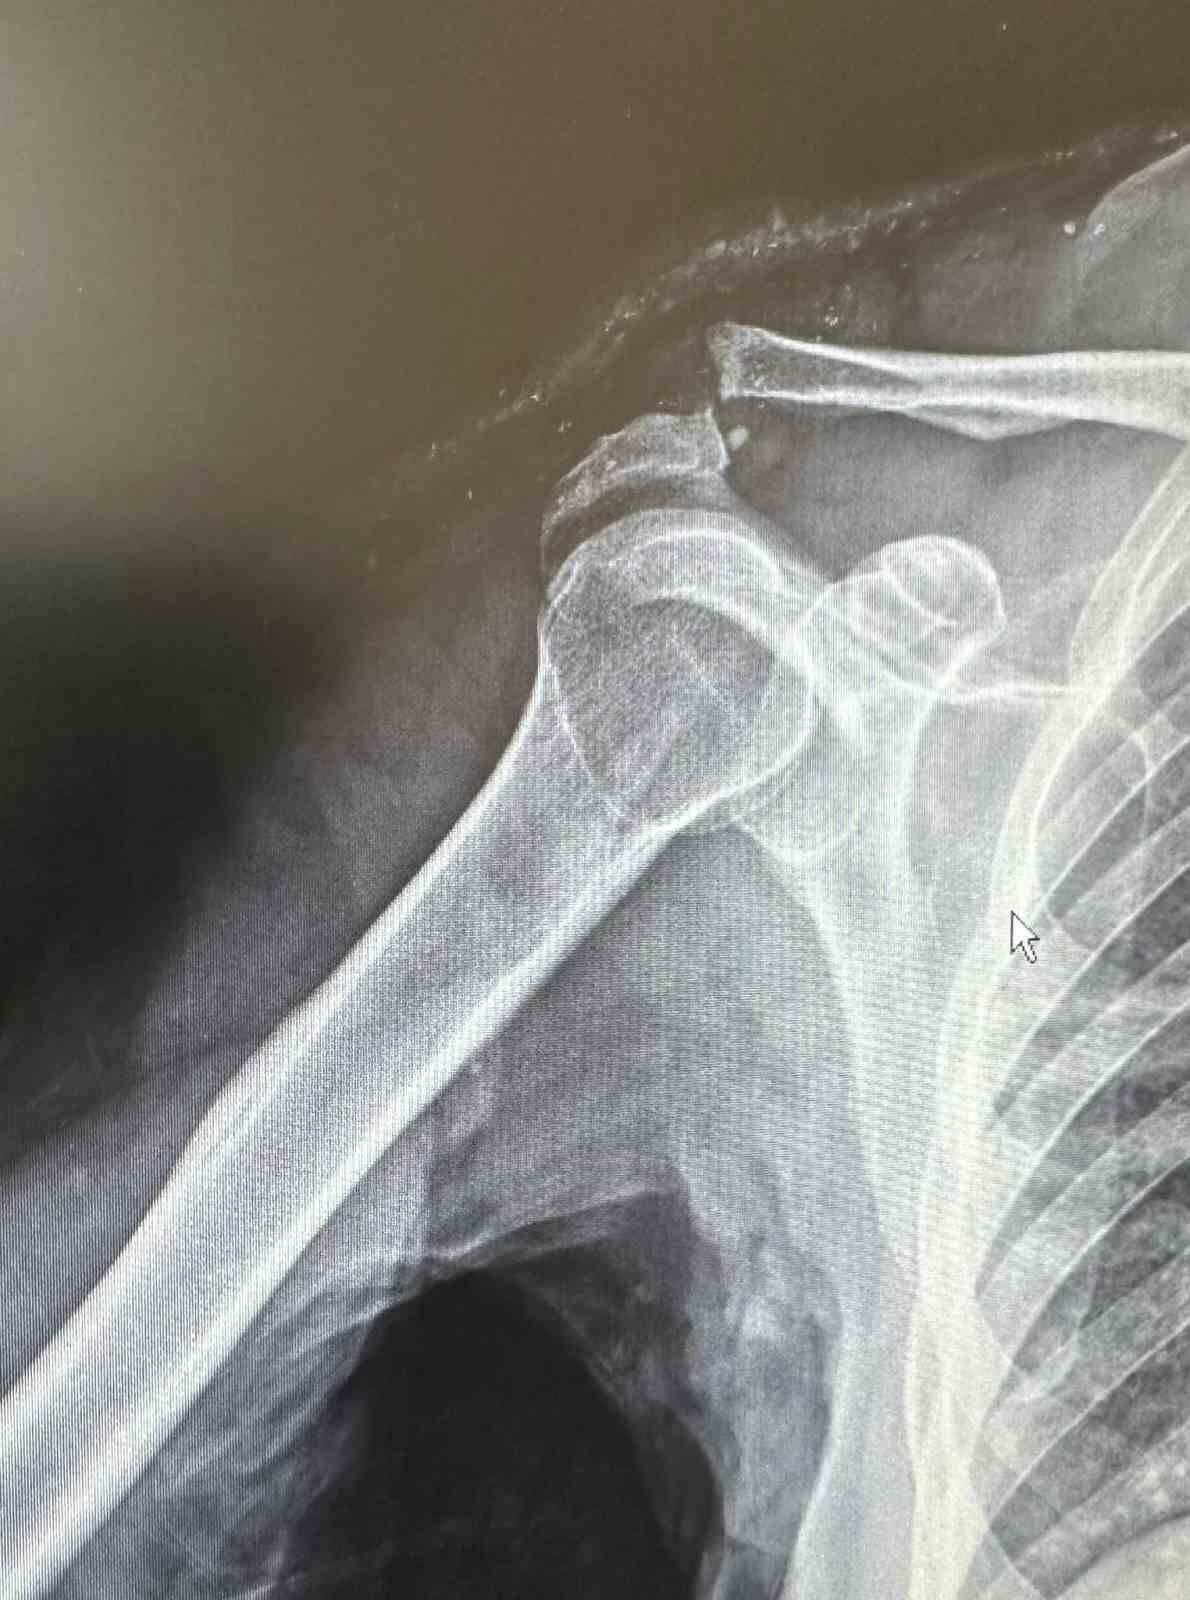

Batman’da 64 yaşındaki Mehmet Şerif Rençber, tenis oynarken omuz çıkığı yaşadı. İleri yaş nedeniyle ameliyat olamayacağı söylense de, Dr. Mehmet Yavuz Başer özel bir plak kullanarak başarılı bir ameliyat gerçekleştirdi. Rençber, ameliyat sonrasında ağrısız bir şekilde eski omuz hareketlerine geri döndü. Hastanın yaşadığı iyileşme, doktorun özenli ve başarılı müdahalesi sayesinde gerçekleşti.

BATMAN’DA, TENİS OYNARKEN OMUZ ÇIKIĞI YAŞAYAN 64 YAŞINDAKİ MEHMET ŞERİF RENÇBER, İLERİ YAŞ NEDENİYLE AMELİYAT OLAMAYACAĞI, KENDİLİĞİNDEN İYİLEŞECEĞİ CEVABI OLMASINA RAĞMEN BAŞKA BİR DOKTORUN ÖZEL PLAK KULLANARAK AMELİYAT ETMESİYLE SAĞLIĞINA KAVUŞTU.

DR. MEHMET YAVUZ BAŞER, HASTANIN 64 YAŞINDA OMUZ ÇIKIĞI NEDENİYLE KENDİLERİNE BAŞVURDUĞUNU SÖYLEDİ.